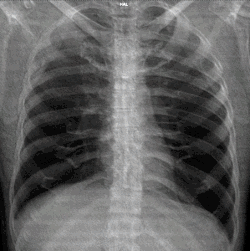

A normal posteroanterior (PA) chest radiograph of someone without any signs of injury. Dx and Sin stand for "right" and "left" respectively.